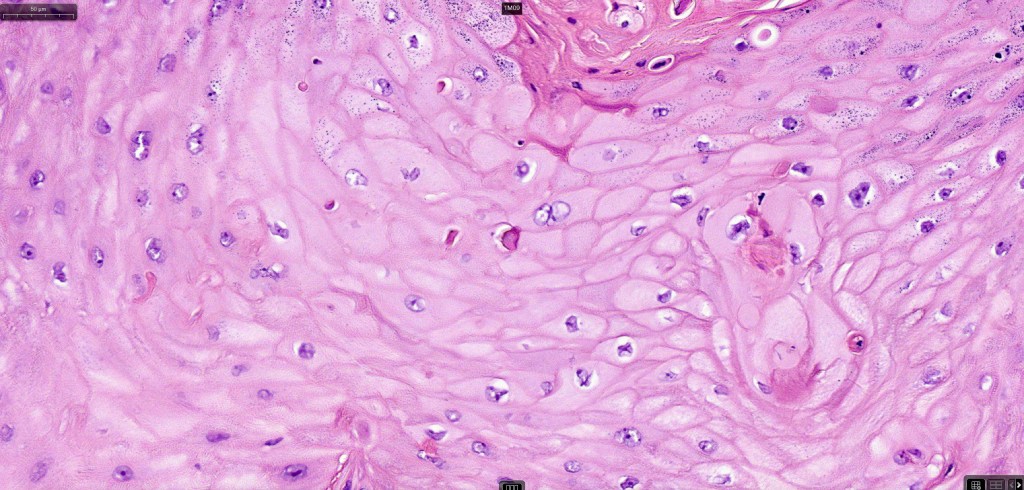

•Keratoacathoma (nowdays regarded as a variant of well differentiated squamous carcinoma) is characterized by a crateriform squamous epithelial lesion (dilated follicular infundibulum) with central keratin plug and adjacent collarette extending to the mid-dermis

•Well differentiated squamous epithelium often with a characteristic ground-glass appearance

•Only mild pleomorphism & basally located mitoses

•Neutrophil-rich microabscesses & necrosis